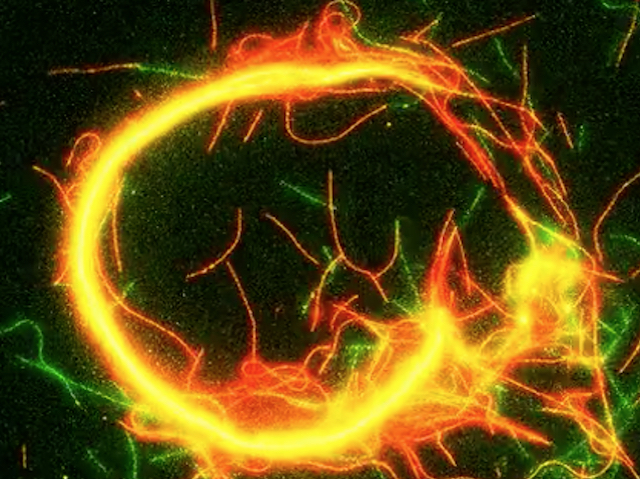

Igual que una persona de la neteja que, davant una queixa per un vessament, es limita a amagar-lo davall de l’estora, les cèl·lules immunitàries del cervell semblen oferir una solució incompleta davant algunes infeccions fúngiques. Els investigadors van estudiar com les microglies de ratolí, les cèl·lules immunitàries residents del cervell, responen a la infecció per Cryptococcus neoformans, un fong que pot causar una meningitis mortal. Van observar que estes cèl·lules detecten el fong dins dels vasos sanguinis abans que travesse la barrera hematoencefàlica, que protegix el cervell. Els fragments alliberats per la càpsula del fong són captats per les cèl·lules que recobreixen els vasos sanguinis, les quals donen l’alarma i demanen ajuda. Les microglies (verd) envolten els vasos sanguinis (rosa) i engoleixen els fongs (roig), però no aconseguixen eliminar-los completament i, fins i tot, poden proporcionar-los un entorn ric en nutrients que afavorix la seua proliferació. Comprendre i, finalment, manipular esta interacció podria conduir a noves estratègies per a tractar o previndre les infeccions fúngiques cerebrals

Imatge del treball de Chenxu Feng, Ge Wang i Yixuan Wang, i col·laboradors/es

Sheng Yushou Center of Cell Biology and Immunology, School of Life Sciences and Biotechnology, Shanghai Jiao Tong University, Shanghai, Xina